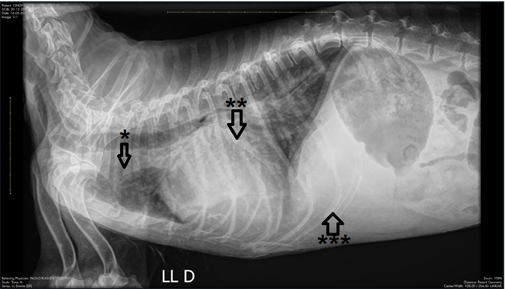

In this case report, a 16 year old female Lhasa Apso dog breed was presented to the clinical facility with signals of apathy, hyporexia, cough and dyspnea. The owner reported that the dog had progressive cough and dyspnea in the last 5 days. The clinical examination revealed that the dog showed apathy, slightly pale ocular mucous membranes and dyspnea; during pulmonary auscultation, characteristic sounds of pulmonary rales were detected. Support with oxygen therapy and administration of furosemide (4 mg/kg every 8 hours intravenously) was started. After stabilization of respiratory condition, imaging tests were performed. The chest radiology showed diffuse pulmonary opacification with an interstitial-alveolar pattern, global increase in the size of the cardiac silhouette and hepatomegaly (Figure 1).

Figure 1 Chest radiography. Diffuse pulmonary opacification of an interstitial-alveolar pattern in the perihilar.

Region of dorsocaudal lung fields (*). Global increase in the dimensions of the cardiac silhouette, more pronounced in the topography of the left chambers (**), dorsally displacing the tracheal path, carina and left main bronchus. Hepatomegaly characterized by hepatic silhouette surpassing the limits of the rib cage (***).

In this case report, the patient had acute pulmonary edema with suspected valvular heart disease involving the left side of heart, which was subsequently confirmed by imaging tests, such as chest radiography.11,12 The radiographic findings of pulmonary edema were more evident in the caudal lung lobes with an alveolar pattern in the middle lobe, accompanied by a change in cardiac silhouette with increased dimensions and dorsal deviation of tracheal path.